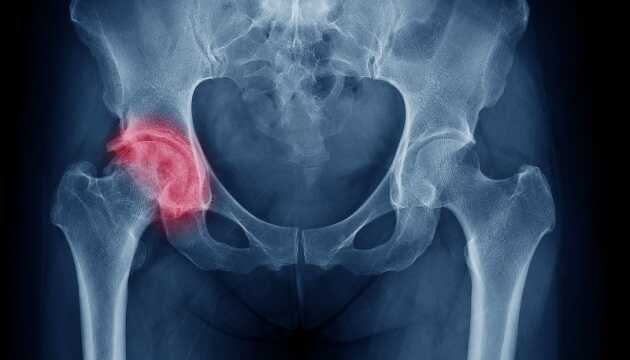

Каждый месяц во время пандемии травматологи 8-й больницы Первого территориального медицинского объединения Львова делают 5-10 операций по замене тазобедренного сустава.

Все пациенты перенесли коронавирус.

«Мы заметили неутешительную тенденцию: пациентов, которым нужна замена тазобедренного сустава, стало значительно больше.

Если до пандемии травматологи 8-й больницы Первого территориального объединения Львова выполняли 5-10 таких операций ежегодно, то сейчас — 5-10 ежемесячно.

И все пациенты болели COVID-19», — говорится в сообщении.